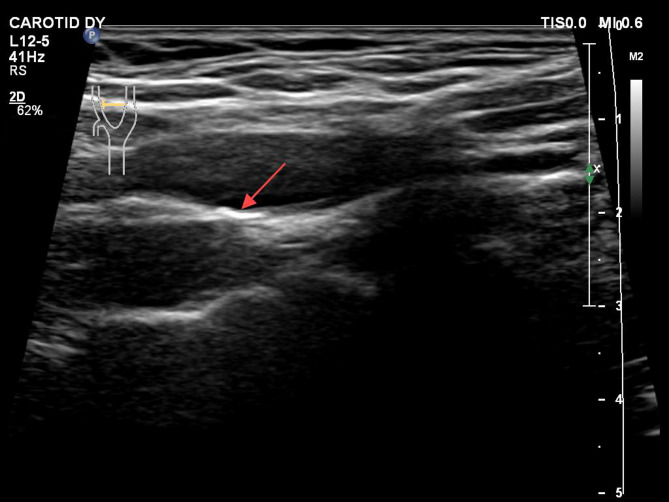

Methods: A total of 838 patients with carotid plaques receiving lipid-lowering therapy were enrolled between July 2020 and May 2024 and followed up for 12 months. Carotid ultrasound was performed at baseline and follow-up to evaluate plaque characteristics. Plaque regression was defined as meeting any of the following criteria: (1) reduction in plaque area ≥ 5%, (2) decrease in plaque thickness ≥ 0.4 mm, or (3) reduction in plaque number, as assessed by vascular ultrasound imaging. Plaque echogenicity was classified into three types: hypoechoic, hyperechoic, and mixed echogenicity. Cox proportional hazards regression analysis was performed to assess the association between plaque echogenicity and plaque regression, adjusting for potential confounding factors.

Abstract Image